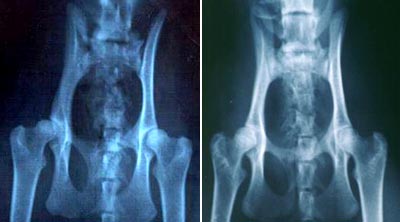

HD - Hüftdysplasie HD

ist eine erbliche, progressive Krankheit des Hüftgelenkes, die hauptsächlich

bei grossen Hunden, aber auch bei grösseren Katzen vorkommt. Bei einem

kranken Tier sitzt das Kugelgelenk nicht mehr korrekt in der Gelenkpfanne,

da diese unterentwickelt ist, und es kann zu erheblichen Beschwerden

bei dem betroffenen Tier kommen. Über die Vererbung dieser Krankheit

ist leider sehr wenig bekannt. Man weiss nur, dass HD polygen vererbt

wird. Aus züchterischer Sicht kann man nur versuchen HD - freie Tiere

miteinander zu verpaaren, da hierbei die Chance sehr viel höher ist,

gesunde Kitten zu erhalten, als bei einer Verpaarung von einem kranken

und einem gesunden Tier oder gar bei Verpaarung von zwei kranken Tieren.

OFA,

2300 E. Nifong Blvd., Columbia, MO 65201-3856, phone number: (314)

442-0418, fax number: (314) 875-5073 Laut

OFA: links "mild" und rechts "exellent"